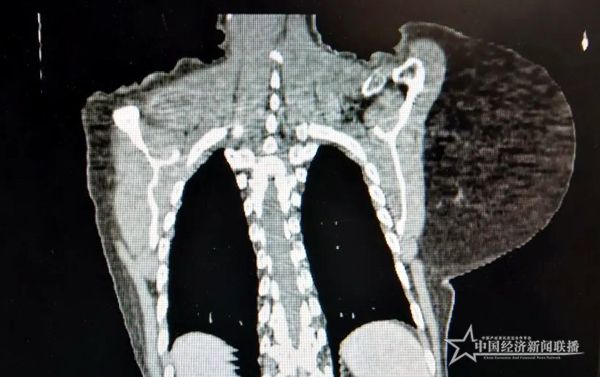

患者在长期重压下,脊柱已经侧弯

因为肿瘤特别大,而且靠近颈部和脊椎,血管神经繁多,且老人合并有多种内科疾病,经过讨论,精心为其制定了最佳手术方案。做足术前准备后,该院颈胸心血管外科团队顺利为其施行肩甲部大肿瘤切除术,完整切除约5斤重肿瘤,帮助患者回归健康人生。